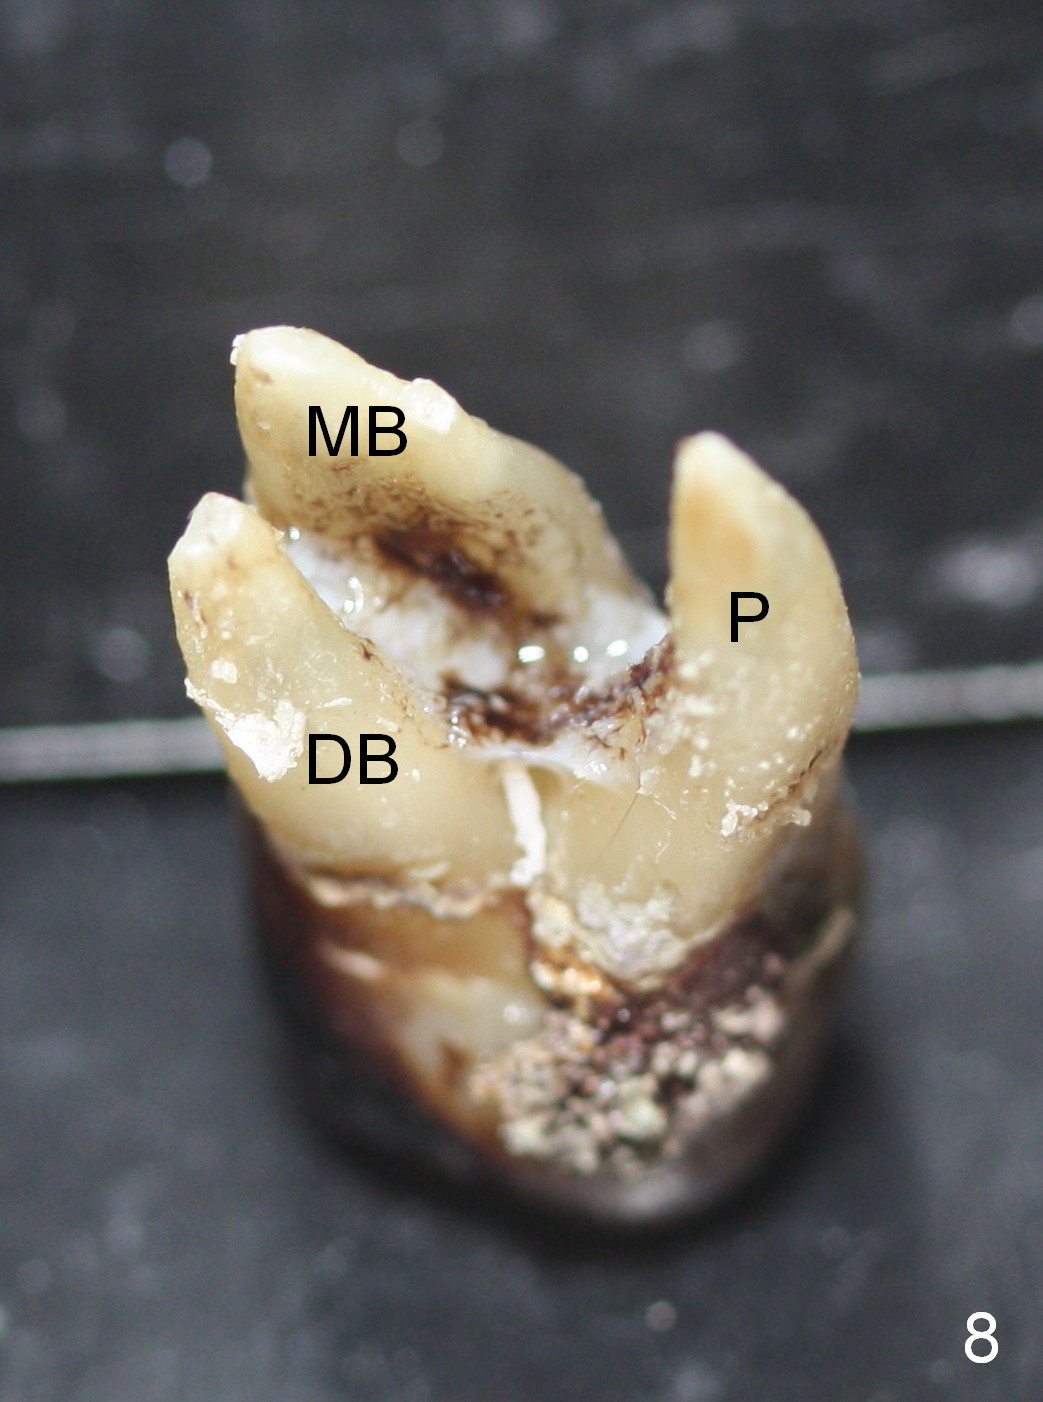

By comparing the root morphology of an extracted tooth (Fig.7,8: #15) with that of X-ray (Fig.9) repeatedly, we can develop an ability to visualize the septum prior to surgery.